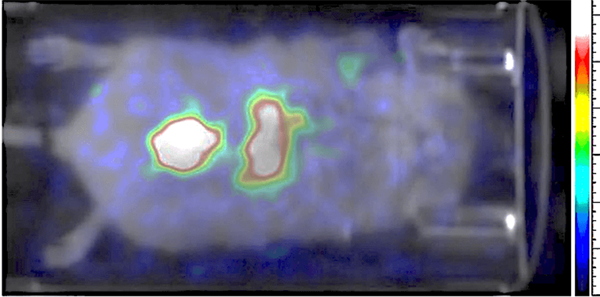

This image shows Tc-99 perfusion imaging in a mouse. This image was acquired in real-time with 1 second frame rate. Image Credit: Scintica Instrumentation Inc.